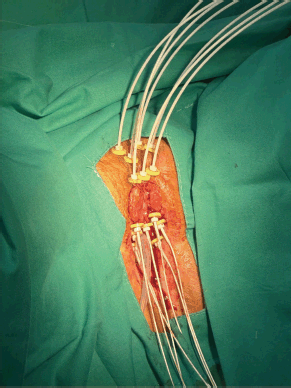

The initial plan suggested possible undercoverage in superficial regions of the tumour (Figure 3). Therefore, a custom silicone bolus containing four additional catheters was placed on the vulvar surface to enhance coverage of peripheral edges. A repeat CT confirmed improved D100 and D90 of the GTV while maintaining urethral dose constraints (Table 1, Figure 4).

Figure 4. Case 1. 3D treatment plan with bolus. The position of the catheters and the dosimetric distribution in the axial, coronal and sagittal planes are observed. On the left, fraction #2 to #5. On the right, fraction #6 to #8. In light blue, the isodose of 5.7 Gy; in white, the isodose of 11.4 Gy.